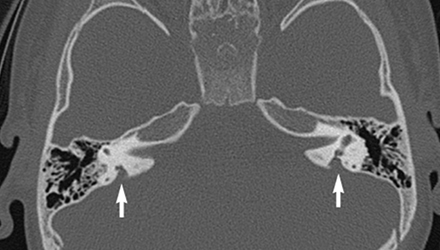

SLC26A4基因定位于人類染色體7q31,SLC26A4基因和大前庭導水管綜合征相關突變位點的發現,證實SLC26A4是大前庭導水管綜合征的責任基因。

我們平時提到的“一巴掌打聾”、“一跤摔聾”其實都與SLC26A4基因突變有關,絕大多數大前庭導水管綜合征都是SLC26A4基因突變惹的禍。

SLC26A4基因突變導致的大前庭導水管綜合征的典型表現為兒童時期的聽力損失,90%的患者為雙側性,聽力損失程度不一,可表現為接近正常或重-極重度。

病程可為穩定性、進行性或波動性,聽力可逐步下降至全聾;跌倒、撞擊等行為或無外界影響都可能引發聽力的下降。